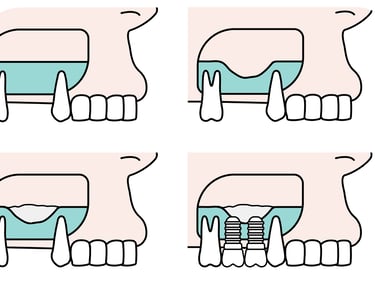

Utiliza plantillas o guías fabricadas con tecnología CAD/CAM para asegurar la colocación precisa de los implantes, minimizando los riesgos y mejorando los resultados.

Colocación de implantes con guía quirúrgica